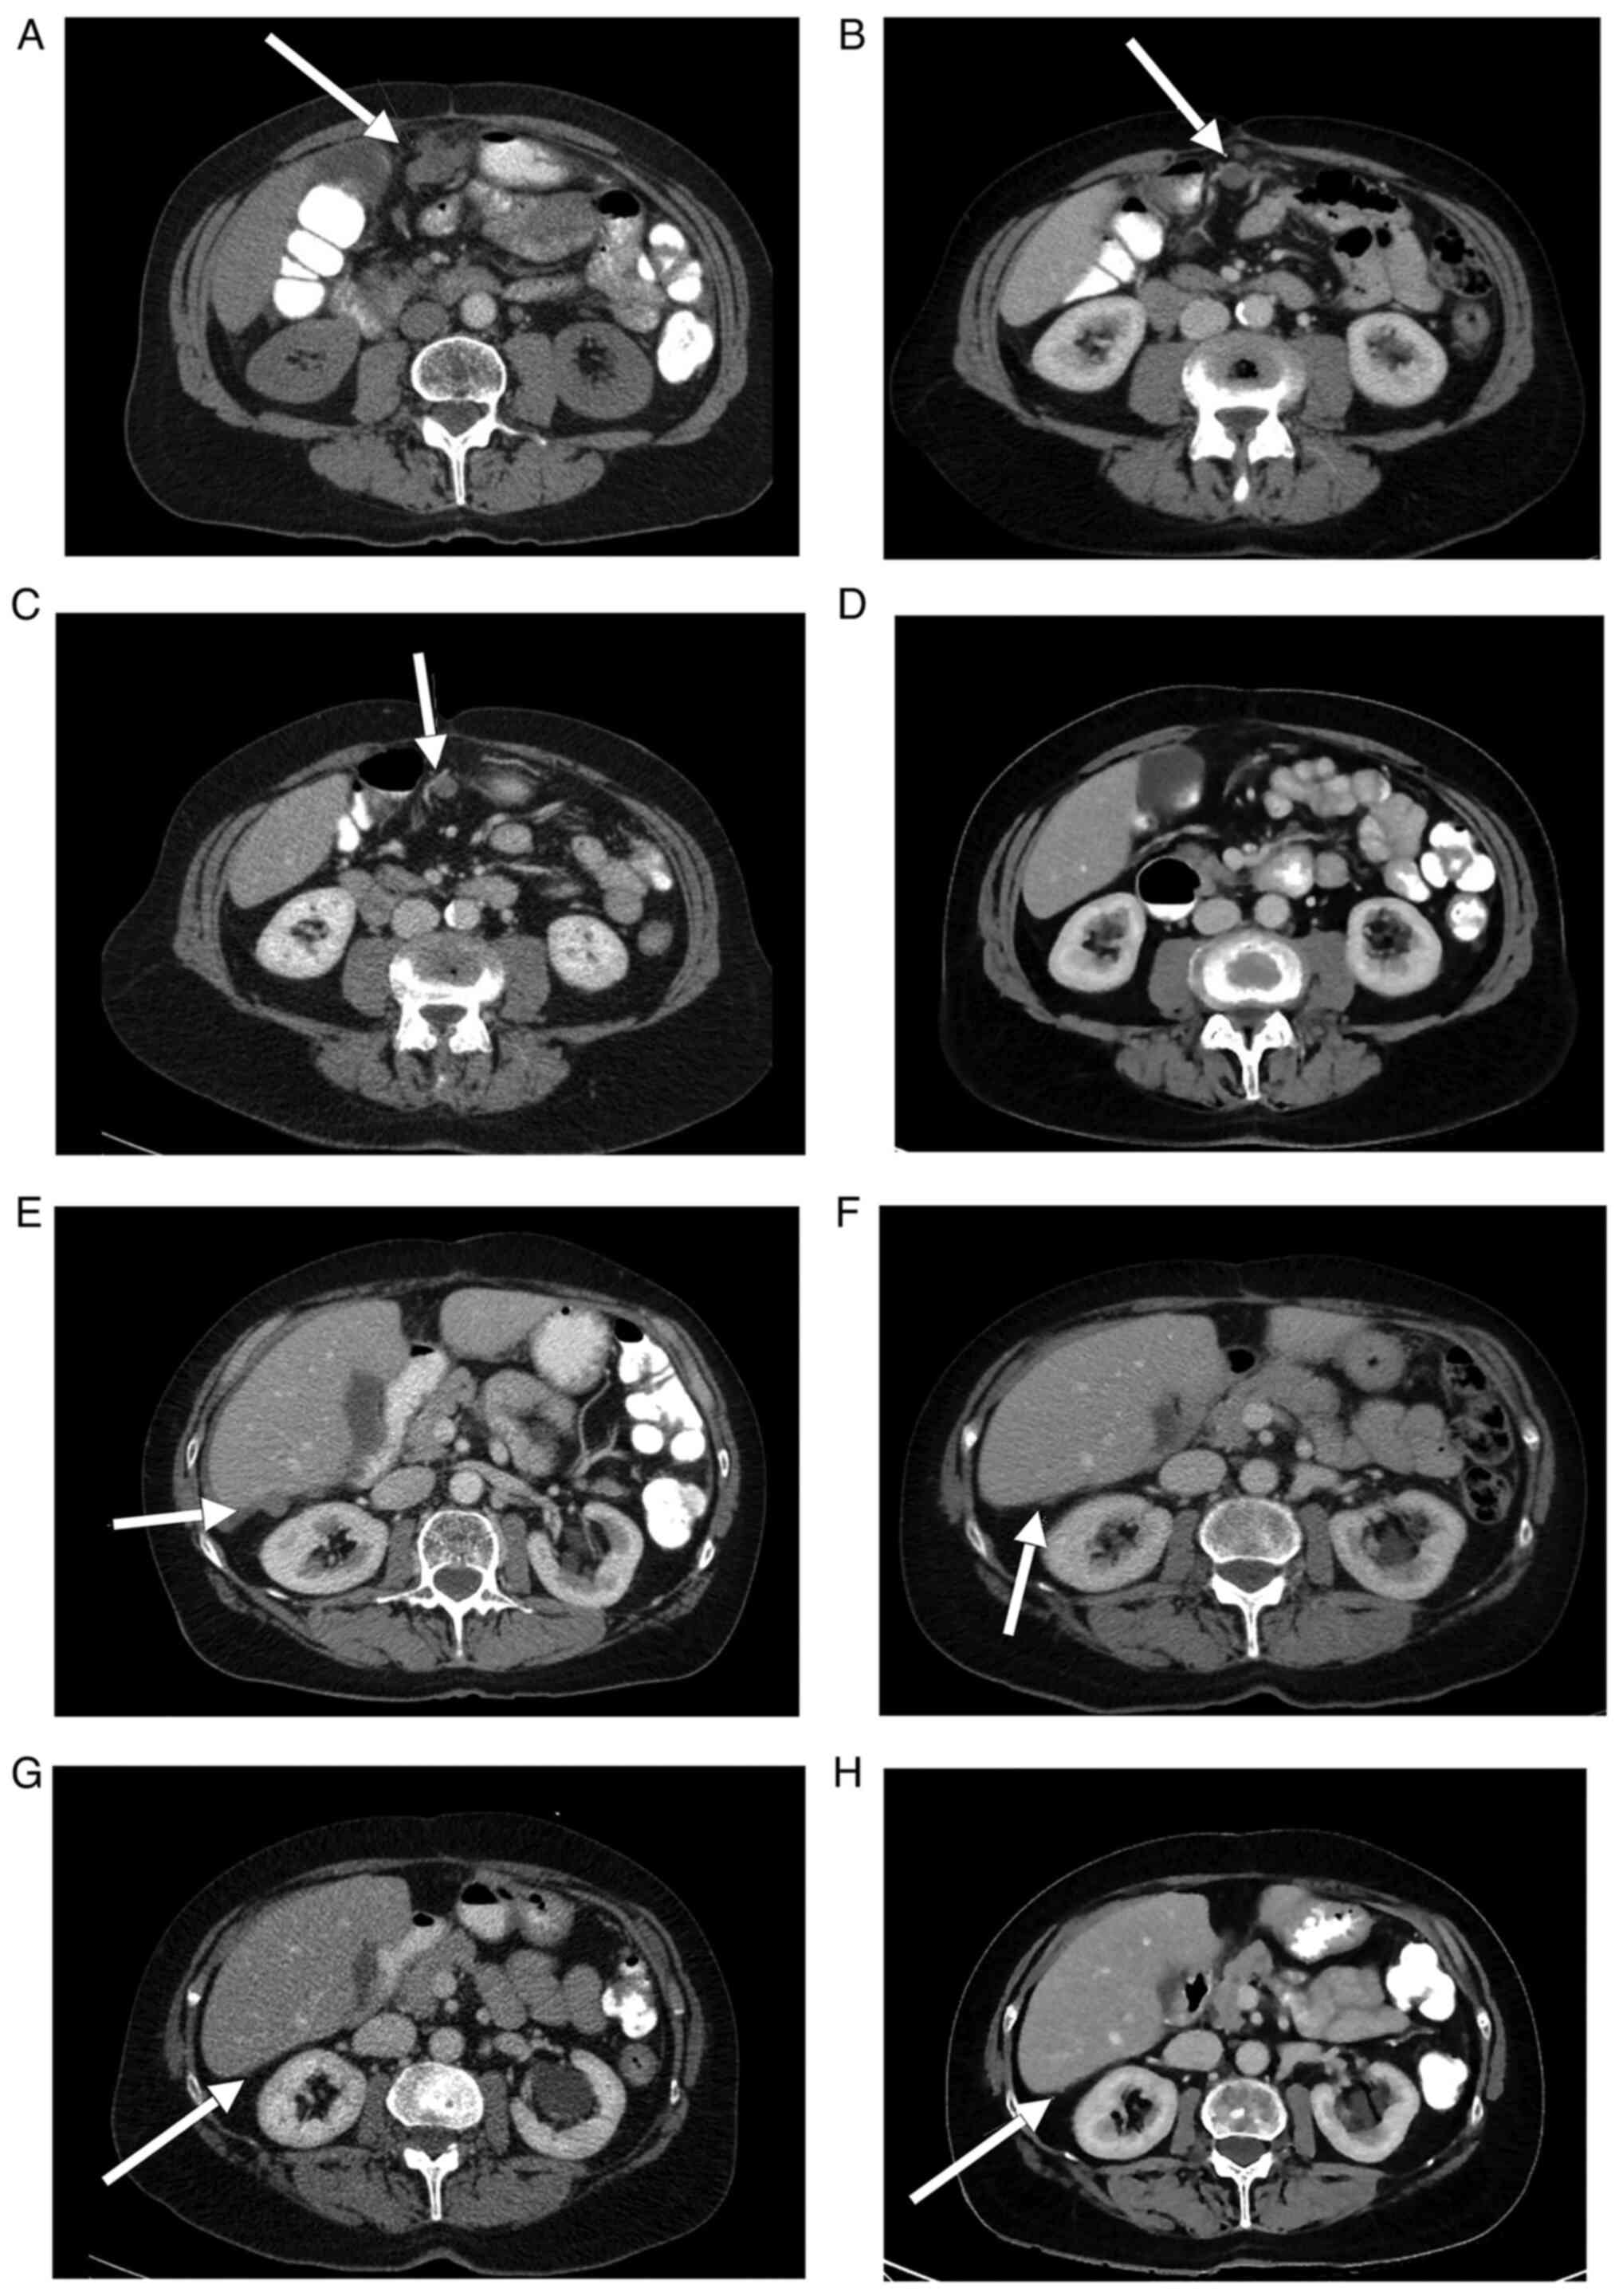

Following a platinum-free interval (PFI) of 12 months, the patient was diagnosed in 01/2010 with the first relapse and was administered re-induction chemotherapy containing six cycles of carboplatin (AUC5) and paclitaxel (175 mg/m²). After three cycles of chemotherapy, she developed a tumor-associated ischaemic covered colon perforation. She underwent a partial colon resection with end-to-end anastomosis and local tumour debulking, which showed histologically vital tumour tissue. She then completed chemotherapy with three further cycles until 05/2010. Her second relapse was diagnosed in 10/2010 following a 5-month PFI. Specifically, the patient developed progressive subdiaphragmal peritoneal metastases compared to 03/2010, newly diagnosed peritoneal metastases on the liver, ascites and right-sided pelvic nodular lesions, as well as metastastic spread below the abdominal wall 1.7 cm above the umbilicus (Fig. 1A-H). Since clinically there was no doubt about the presence of a second recurrence due to the tumour spread pattern, furthermore there was still no possibility of operating on the patient macroscopically completely tumour-free and as the patient was to be saved expected complications, histological confirmation of the second recurrence was not performed.

Figure 1

(A-D) Computed tomography imaging demonstrating the regression of a lesion of peritoneal carcinomatosis on the anterior abdominal wall (arrows) prior to the initiation of PARPi therapy on January 13, 2011 and the patient follow-up on March 2, 2011, November 7, 2012 and November 30, 2015. (E-H) Computed tomography imaging indicating the regression of a perihepatic lesion of peritoneal carcinomatosis (arrows) prior to initiation of PARPi therapy on January 13, 2011 and the follow-up on March 2, 2011, November 7, 2012 and November 30, 2015.

Due to her cancer history, which was associated with a significant familial cancer burden, a BRCA1/2 germline analysis was recommended. The patient suffered from bilateral breast cancer of the left side in 1987 and of the right side in 1999. She was treated with bilateral mastectomy and double CMF chemotherapy followed by endocrine therapy from 1987 to 1992 (20 mg tamoxifen/d) and from 1999 to 2002 (2.5 mg letrozol/d). Her family history indicated that one of her two dizygotic twin daughters, born in 1970, was diagnosed with a triple-negative breast cancer at the age of 38 years, and her maternal aunt was diagnosed with breast cancer at the age of 75 years (Fig. 2). The patient demonstrated a heterozygous pathogenic nonsense mutation (c.5857G>T (p.Glu1953X) in exon 11 of the BRCA2 gene (Fig. 3). Due to the mutation status and after obtaining her written informed consent, the patient was included in the ICEBERG 2 study (phase 2 study to assess the efficacy and safety of the PARPi olaparib for the treatment of BRCA-positive advanced OC) in January 2011, with 400 mg olaparib/2x per day prior to cytoreductive surgery or chemotherapy. The ethical approval regarding the inclusion of patients in the study was received from the Ethics Committee of the University Hospital of Cologne (EudraCT-Nr. 2010-022278-15, Protokoll-Nr. D0810C00042). During the first staging period, which occurred 8 weeks after enrollment, the patient exhibited a partial response as evidenced by CT imaging (small residual findings) and decreased levels of the tumor marker CA-125 (from 142 kU/l in January 2010 to 7 kU/l). Re-staging was performed every 8 weeks within the first 6-month period and subsequently every 12 weeks until the end of the study in November 2015. The assessment included CT of the abdomen/thorax and tumor marker controls (CA-125 and CA-153) without any sign of relapse (Fig. 1A-H). Since 2015, the patient has remained symptom-free and is subjected to regular tumor marker level measurements (CA-125 and CA-153, Fig. 4), which have been within the normal range (<35 kU/l). The results of additional examinations (haematology, clinical chemistry and urinanalysis) have also been within the normal range. Gynecological and physical examinations, including sonography, indicate no suspicion of relapse. The patient has remained relapse-free for 10 years (close-out visit: 12.07.2021, patient has given her written consent tot he publication of this case report). Therefore, PARPi therapy was associated with optimal efficacy and tolerability.